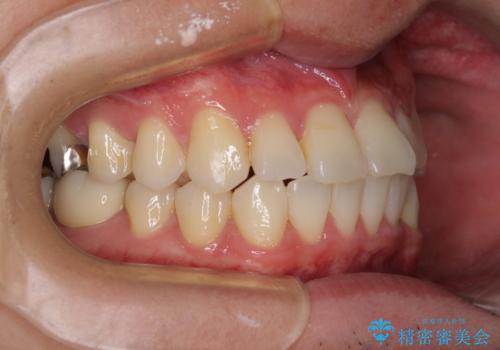

- 右下奥歯の虫歯がしみて痛いとのことで来院された患者様です。

神経近くにまで及ぶ大きな虫歯でしたが、速やかに処置を行い、痛みは即日解消されました。

虫歯が大きかったため、クラウンによる補綴治療が必要になる旨をお伝えしたところ、矯正治療にも興味があるとのことでした。

短期間で手間のかからない方法がご希望でしたので、ワイヤー装置による矯正治療を行うこととし、矯正治療後に右奥2歯をセラミッククラウンにて補綴することとしました。